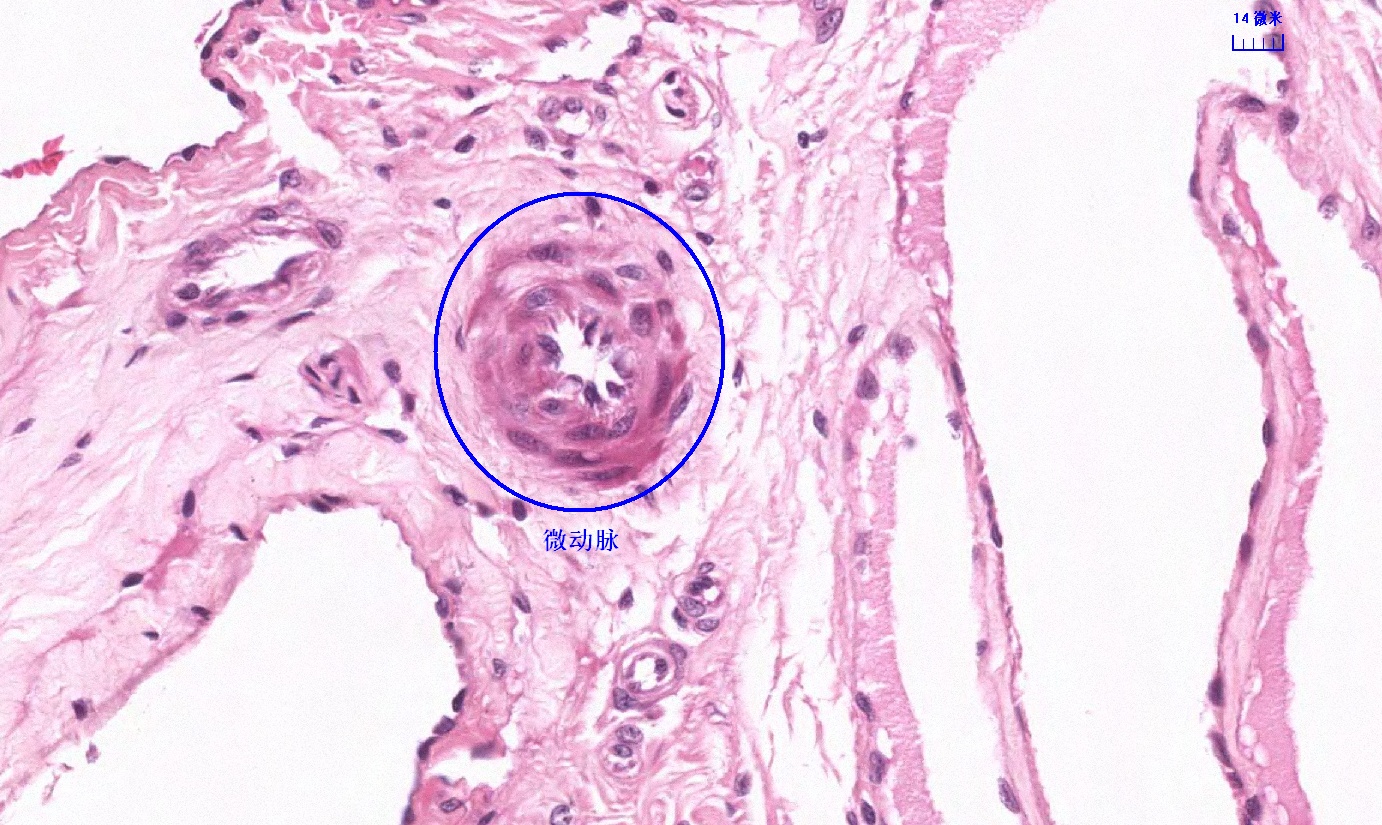

6.1 循环系统切片库

6.2 循环系统微课

6.3 循环系统课件